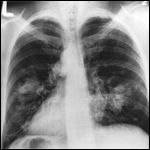

Both sides of the lungs are visible with a growth on the left side of the lung, which could be lung cancer.